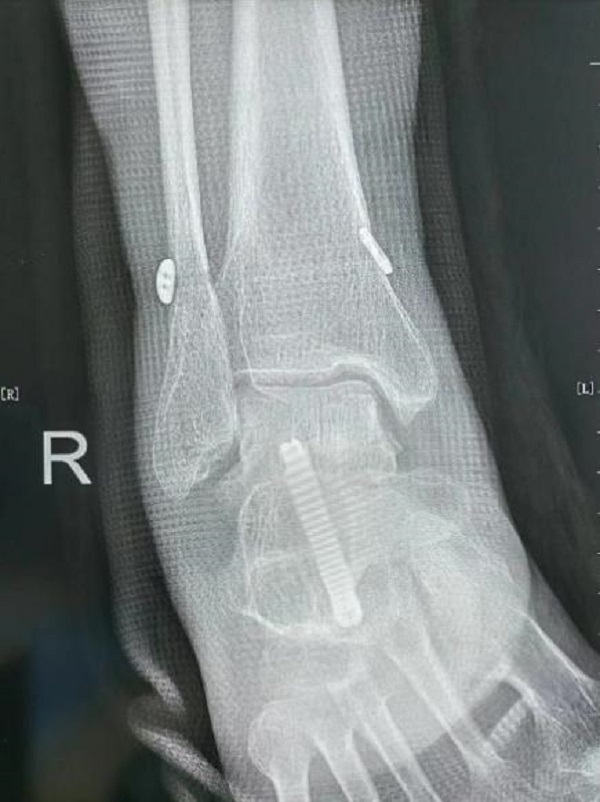

术后影像学资料